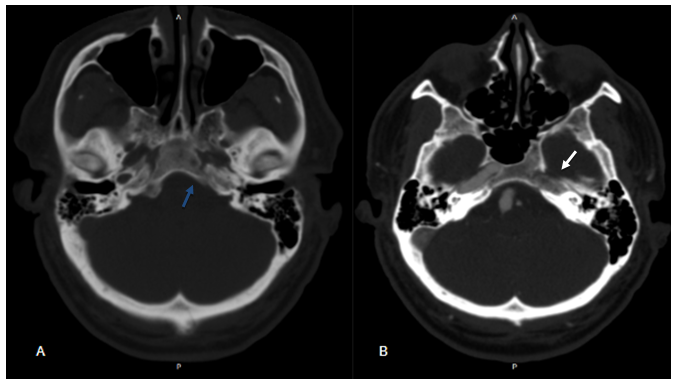

A 57-year-old male patient, asymptomatic, with a history of a car accident, in the investigation of head trauma. CT and Angio-CT show the absence of the left carotid canal and non-opacification of the left ICA (Figure 1 A & 1B). Other findings are the fenestration and fusiform aneurysm of the basilar artery (BA) with a prominent left posterior communicating artery (PCoA) continuing in the middle cerebral artery (MCA) (Figure 2 A & 2B). Digital cerebral angiography confirmed the findings described and demonstrated that the left middle cerebral artery was supplied by BA through the ipsilateral posterior communicating artery (Figure 3A & 3B). We consider the demand for flow in the territory of the left MCA by the Type I agenesis of the ICA as a pathophysiological mechanism related to the development of the fusiform aneurysm of BA. Option for conservative treatment of the flow-related aneurysm.

Figure 1 (A) CT without contrast showing absence of the left carotid canal (blue arrow). (B)– Angio-CT showing non-opacification of the left internal carotid artery (ICA) and absence of the ipsilateral carotid canal (white arrow).